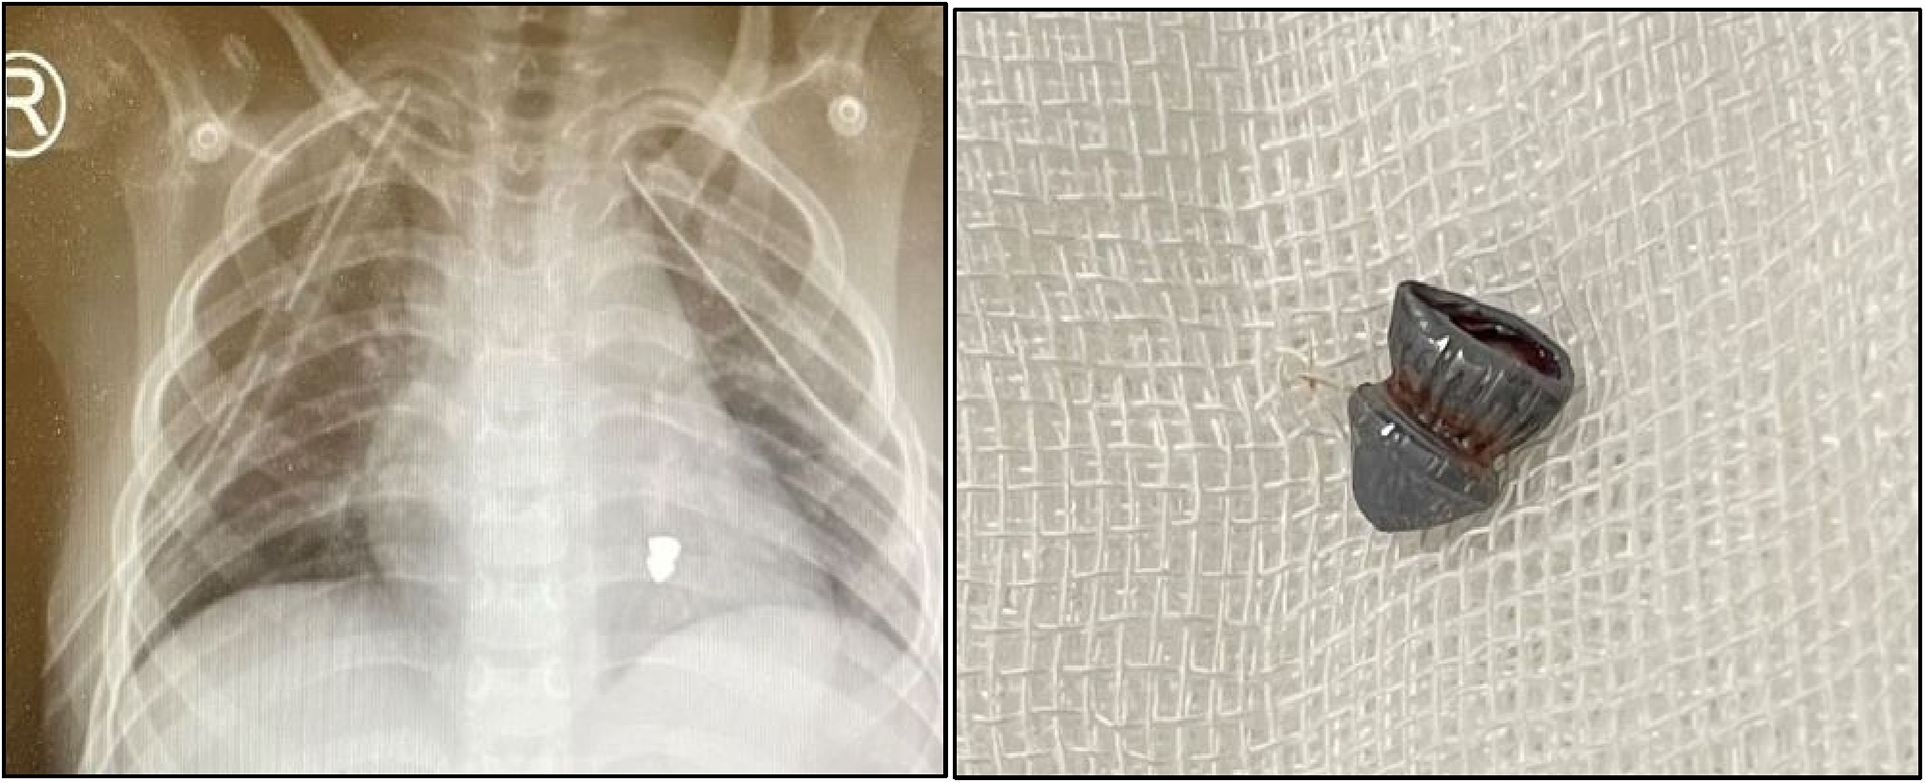

The presented case report describes a 7-year-old boy without history of other medical concerns who was brought to the emergency unit after sustaining a single gunshot wound to the right side of his chest, resulting from an assault accident while on his way to school. There was no exit wound. Despite complaining of thoracic pain, the boy remained conscious and exhibited vital signs, including a blood pressure of 116/79 mm Hg, a pulse rate of 118 beats per min, and a respiratory rate of 38/min. After examination by a general surgeon, a chest tube was placed in the damaged thorax (right), and a small amount of blood and air were released. Further examination following the relative stability of hemodynamics revealed an entrance wound near the right side of the sternum at the level of the third intercostal space. There was no marked subcutaneous emphysema or jugular venous distention. His initial hematocrit was 32%. Arterial blood gases did not detect hypoxemia or acidosis, and an electrocardiogram showed normal sinus rhythm. Upon conducting a chest radiograph (CXR) and computerized tomography (CT) scan, it was determined a bullet (5.5 mm long) was in the left part of the mediastinum (Figures 1, 2). Therefore, a pleuropericardial window is installed through the left thoracotomy, which removes some blood and clots from the pericardium. After completing these procedures and receiving intravenous fluids, the patient's vital signs became completely stable, and he was referred to the local hospital with a cardiologist for further investigation, where echocardiography was performed and placing the bullet in the left ventricle was confirmed. Considering the risk of embolization, the patient is sent to the tertiary referral hospital. Transesophageal echocardiography (TEE) showed that the right atrium and ventricle were functioning normally, with a thick particle in the left ventricle (LV) cavity behind the posterior leaflet and mild mitral regurgitation (MR). No aortic insufficiency (AI) or pulmonary vein (PV) stenosis were also observed. In addition, high-resolution computed tomography (HRCT) revealed left pleural effusion, scattered sub-segmental atelectasis in both lungs, and bilateral mild pneumothorax. Due to the possibility of bullet embolization, the patient underwent elective surgery to remove the foreign body from inside the heart. The surgical procedure was conducted via the median sternotomy approach. A partial thymectomy and pericardial opening were performed. The quantity of blood and clots evacuated from the pericardium Although dissection of the mediastinum and the great vessels was challenging, it was executed without harm. The entry point of the bullet was found in the anterosuperior part of the lower right pulmonary vein, which was covered by a clot. After the right atriotomy, the interventricular septum was split, and the bullet stuck in the posterior chordal lobe of the mitral valve was released and removed (Figure 3). Then the septum between the atrium and right atrium and the pulmonary vein are damaged and repaired, and after coronary perfusion is established and normal heart contractions return, cardiopulmonary bypass is stopped and the chest wall is repaired (Figure 4). Following the closure of the sternum, the patient was transferred to the intensive care unit and was deemed to be in stable condition. The patient underwent extubation within the initial 24 h following the surgical procedure. The individual achieved full recuperation and was released from medical care after 14 days. During a subsequent 6-month evaluation, the patient continued to exhibit a state of well-being, and there were no symptoms or signs of cardiothoracic infection or evidence of MR in echocardiography.

Figures 1, 2

According to the CXR, a bullet of 5.5 mm in length was found in the anteroposterior of left part of the mediastinum, gunshot.